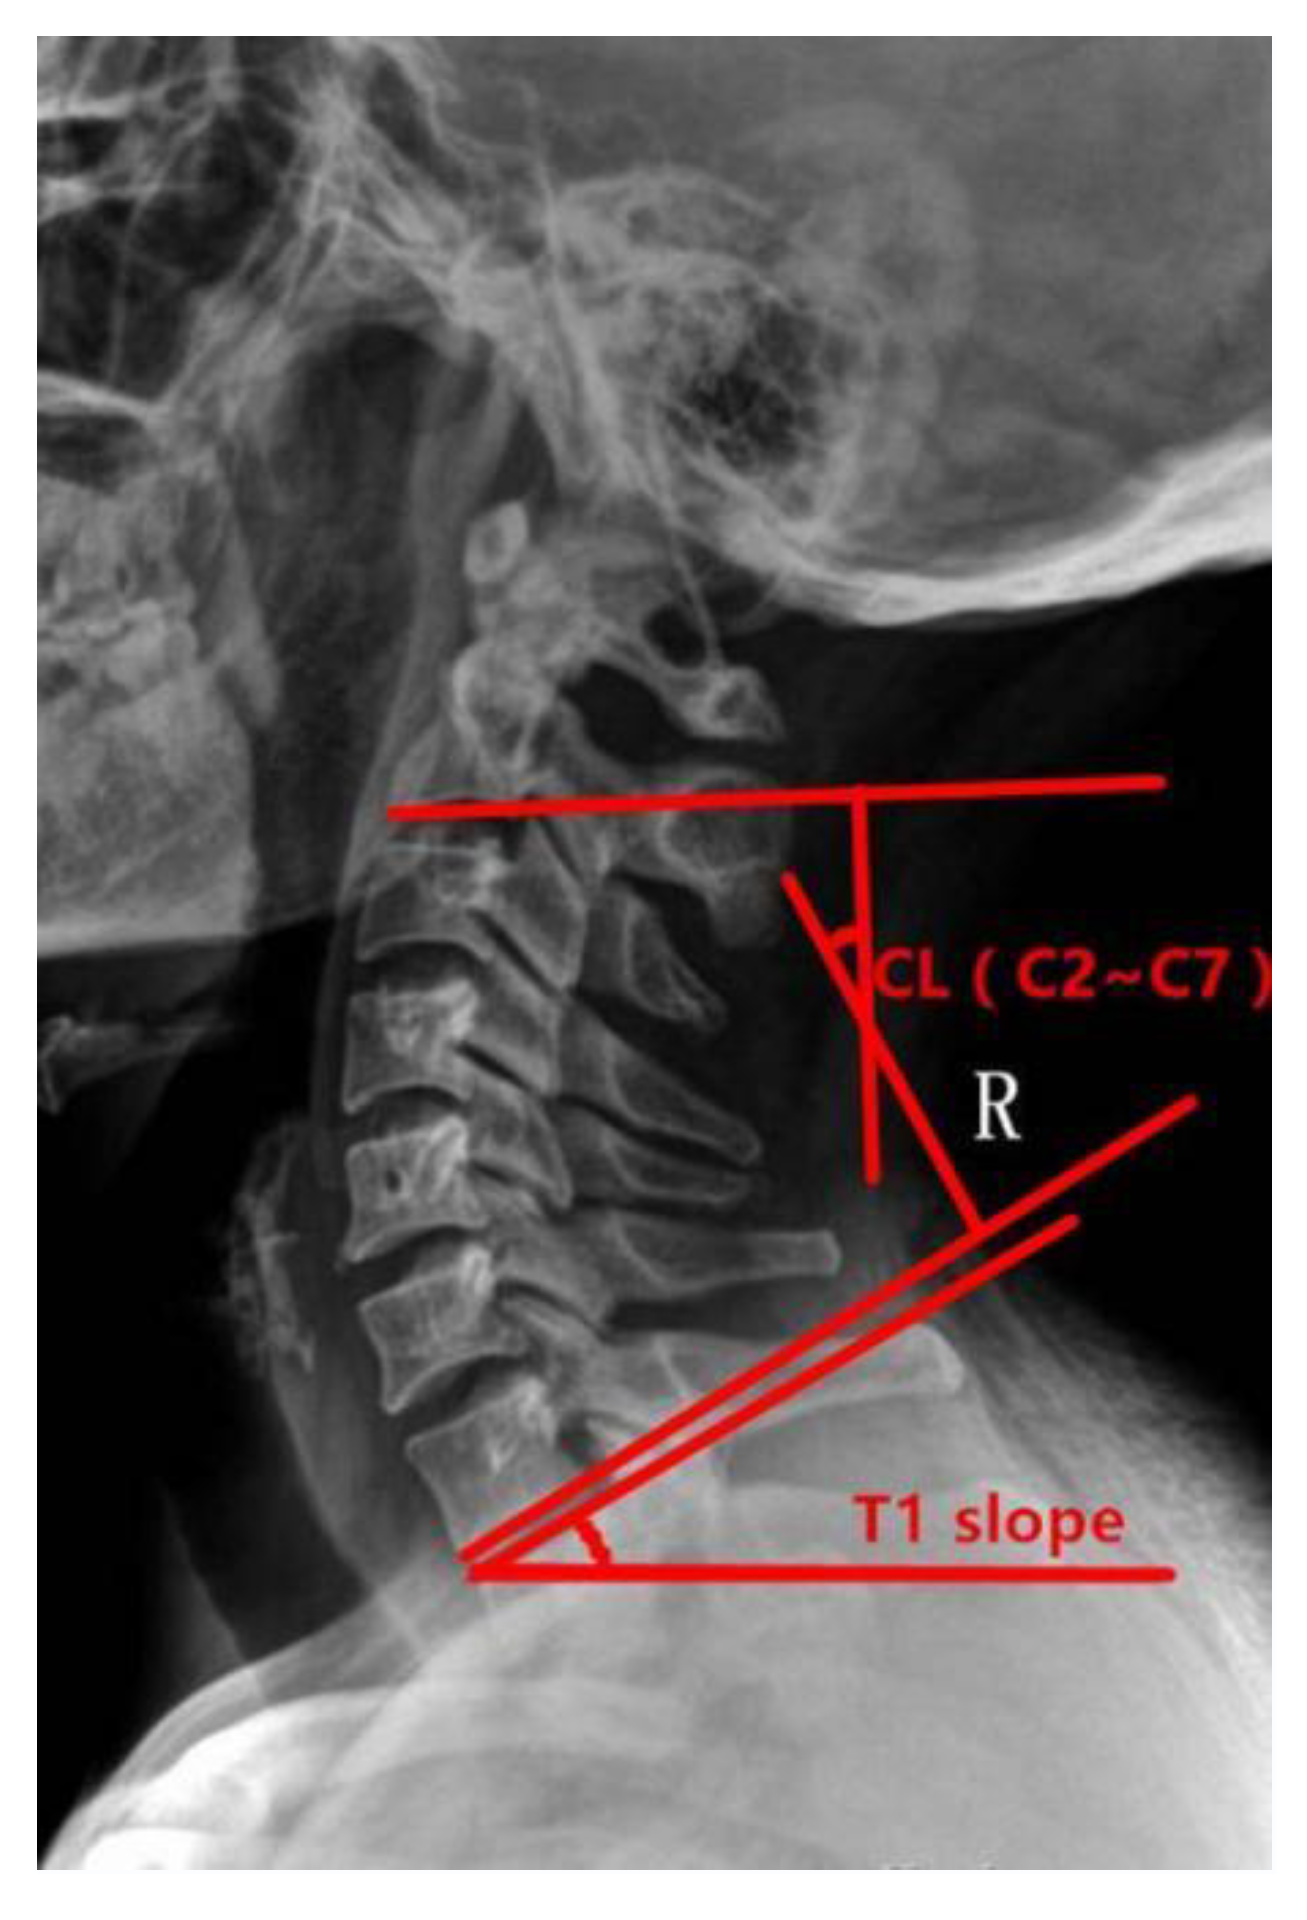

Figure 1.

Preoperative T1s determination method used in the study. The angle between the upper edge of T1 and the horizontal line was measured.